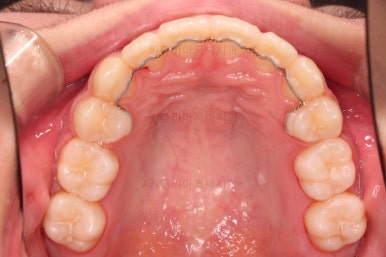

우선 윗니만 장치를 부착했습니다.

순서는 윗니 장치 부착 후 발치를 하고, 가지런하게 된 뒤에, 과개교합 개선을 위한 특별한 장치가 들어가면서 아랫니에도 브라켓을 부착하기로 정했습니다.

이번 환자분이 선택한 장치는 엠파워 메탈이라고 하는 자가결찰 금속 브라켓입니다.

부산치아교정치과 키다리아저씨치과에서 마무리한 입안의 모습입니다.

가지런하게 잘 정렬이 되었고요.

윗니만 발치한 편악발치교정이지만 틈새 없이 공간이 닫혔으며 교합도 잘 맞습니다.